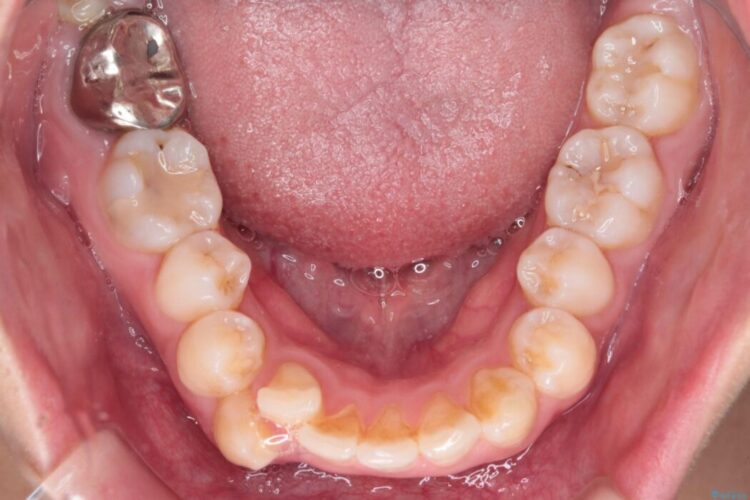

前歯から奥歯にかけて重度のがたつきを主訴にご来院された患者様です。

スペースが大きく不足し、口元を引っ込める必要があったため、上下左右4本抜歯による矯正治療を計画。目立たないインビザライン装置で、審美的なゴールを目指します。